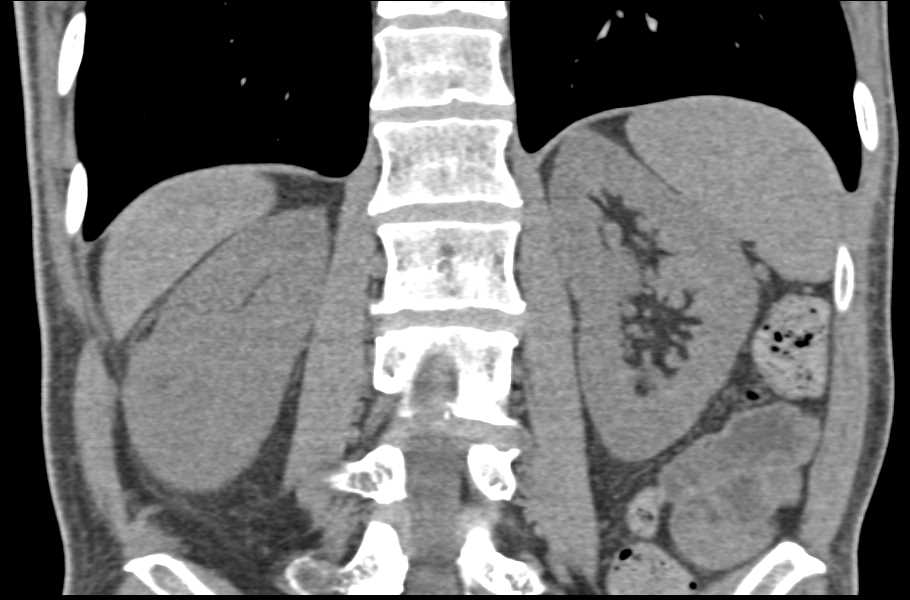

Obstruction with Tumor at the Left Ureterovesical Junction (UVJ)